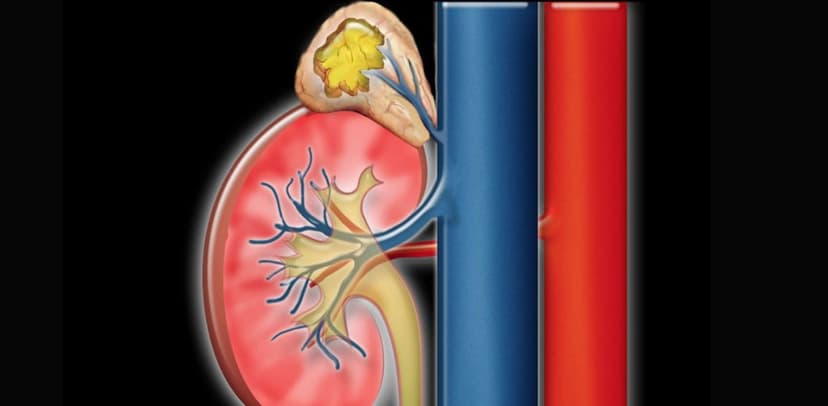

Tuyến thượng thận có cấu tạo gồm vỏ thượng thận và tủy thượng thận. Tùy thuộc vào nơi khối u phát triển và loại hormone khối u tạo ra mà người bệnh có thẻ có các triệu chứng khác nhau.

Hình ảnh mô tả khối u tuyến thượng thận trên giải phẫu và trên hình ảnh siêu âm.